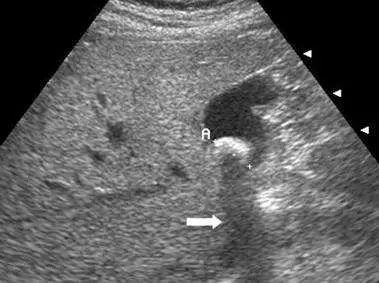

附圖為上腹部超音波影像,箭號所指為下列何者?

本題考查超音波假影(ultrasound artifact)的辨識,重點在於辨認上腹部超音波影像中箭號所指的特定假影。正確答案為音波陰影(acoustic shadowing),這是超音波遇到高衰減係數結構(如膽結石、骨骼)時所產生的典型假影。

影像為上腹部橫切面超音波,可見膽囊(gallbladder)區域,膽囊內出現強回音(hyperechoic)的結構,代表膽結石(gallstone)。箭號指向膽結石後方的一條黑暗帶狀無回音區,向下延伸,這就是音波陰影(acoustic shadowing)的典型表現。影像右側可見幾個三角形箭頭標記(arrowheads),指向膽囊邊緣。陰影邊緣清晰乾淨(clean shadow),為膽結石等鈣化結構的特徵。

(A) 彗尾假影(comet tail artifact) 彗尾假影屬於混響假影(reverberation artifact)的一種,由兩個緊密間隔的強反射面之間反覆反射所產生。外觀呈三角形、錐狀的強回音尾巴,由近而遠逐漸減弱消失(tapered tail),常見於膽囊壁膽固醇結晶(cholesterol crystal)或金屬針頭。特徵是向深部逐漸變細消失,而非形成黑暗帶狀陰影。本圖不符合。